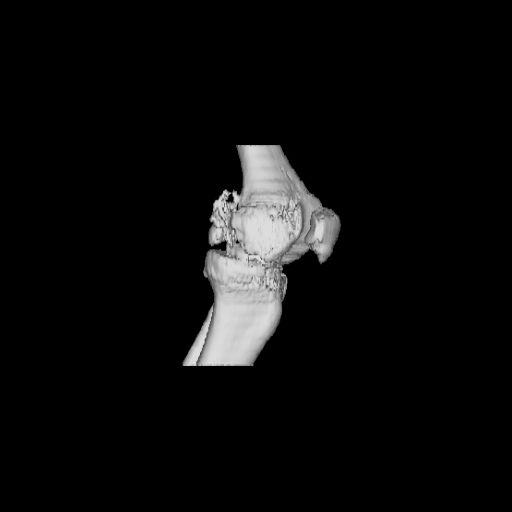

При внутрисуcтавных переломах трехмерные (3D) изображения, кроме красивого снимка, не дают полную информацию о состоянии отломков, самыми информативными являются корональные срезы на КТ и обычная длинная ренгенограмма конечности для сравнения оси конечности.

Фронтальные внутрисуставные переломы мыщельков бедра, так называемые Hoffa fracture, не частые, но встречающиеся переломы, в основном они связаны с травмой высокой энергией.

Даже при сросшемся переломе мыщелка рекомендуется реконструктивная операция для предотвращения последующих варус или вальгус деформации.

Место образовавшего костного дефекта после разворота мышелка заполняется спонгиозной аутокостью. Костная пластика применяется даже

в свежем случае.

Под наркозом редрессация, ранняя разработка сустава после операции, нагрузка на конечность через 12 недель помогут удержать без коллапса

фиксацию и поможет больному восстановить функции конечности без артропластики коленного сутава.